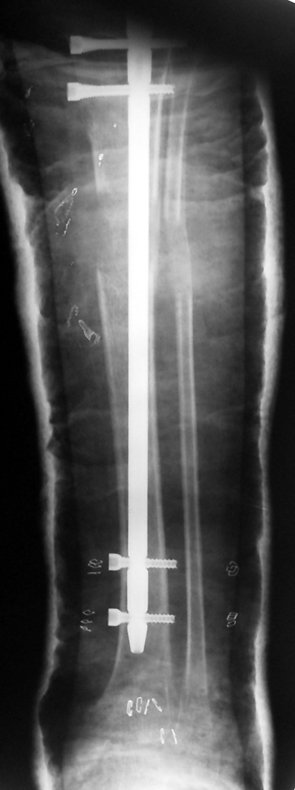

Bu Bacak Kısalık tipi bir kırığın kısalmış pozisyonda kaynaması ile oluşur. Bir çok vaka yetişkinlerde görülür ve sadece bir uzatma ile tedavi edilebilir. Ek deformiteler de aynı anda düzeltilebilir. Bu hastaların çoğu çivi üzerinden uzatma veya tam implante edilen çivi ile tedavi edilebilirler.